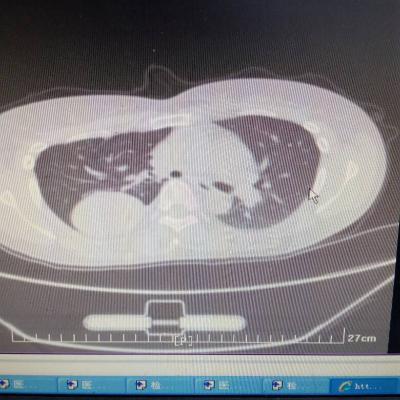

1.胃食管反流病 1.1反流性食管炎LA-B 2.食管裂孔疝 处理:患者诊断明确,行腹腔镜下食管裂孔疝修补术+胃底折叠术。

患者术后一周出院,反酸、烧心、嗳气症状明显缓解,无吞咽不畅等症状。 讨论:对于诊断有食管裂孔疝病人的胃食管反流病,且用药有一定疗效,建议行手术治疗,行腹腔镜下食管裂孔疝修补术,修补了膈裂孔,同时行胃底折叠术,加紧了贲门括约肌压力,共同形成抗“反流瓣”。